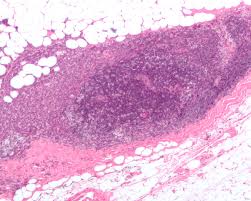

Types Of Breast Cancer Breast Pathology Johns Hopkins Pathology

Types Of Breast Cancer Breast Pathology Johns Hopkins Pathology from pathology.jhu.edu